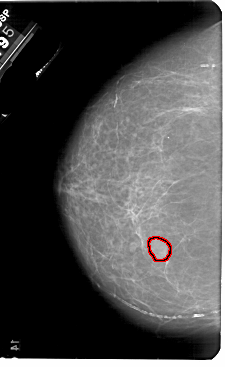

A_1836_1.RIGHT_CC

RIGHT_CC LINES 5491 PIXELS_PER_LINE 3181 BITS_PER_PIXEL 12 RESOLUTION 43.5 NON_OVERLAY

FILE: A_1836_1.LEFT_MLO.OVERLAY

TOTAL_ABNORMALITIES 1

ABNORMALITY 1

LESION_TYPE MASS SHAPE OVAL MARGINS OBSCURED

ASSESSMENT 3

SUBTLETY 5

PATHOLOGY BENIGN

TOTAL_OUTLINES 1

BOUNDARY